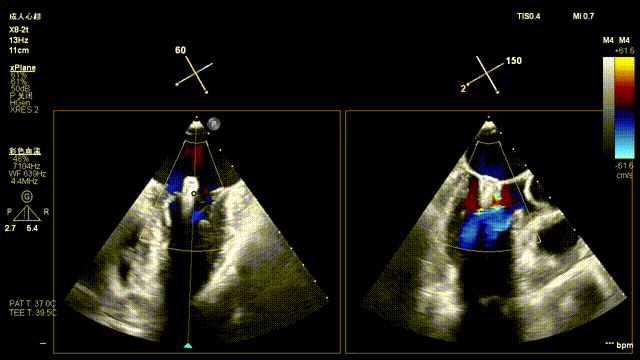

Tricuspid Valve Annuloplasty Stage:Subsequently, via the right internal jugular vein approach, the K-clip® transcatheter tricuspid valve annuloplasty system was delivered to the right atrium. With the assistance of three-dimensional ultrasound stereoscopic views, a 12T clip was successfully implanted at the posteroseptal commissural annulus of the tricuspid valve, and a 14T clip at the anteroposterior commissural annulus, achieving effective constriction of the dilated annulus. Immediate postoperative assessment demonstrated that tricuspid regurgitation was improved from severe (4+) to mild (1+) instantaneously.

1.Intraoperative baseline assessment of regurgitation severity

5.Perform the same procedure for the second clip; the clip morphology is stable under 3D imaging

Annuloplasty Effect: The tricuspid valve annulus area was reduced from 9.96 cm² to 4.6 cm², representing a 53% decrease in annulus area.

Preoperative regurgitation (severe)

Postoperative regurgitation (trivial)

Surgical Outcome: Severe tricuspid regurgitation (4+) was reduced to mild tricuspid regurgitation (1+).